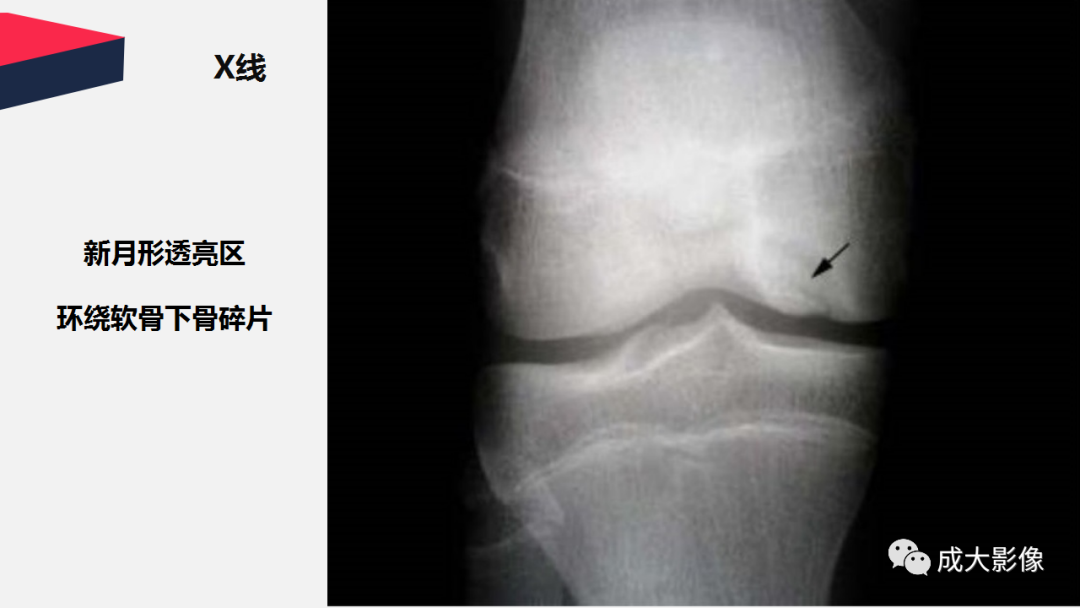

【PPT】剥脱性骨软骨炎-4

【PPT】剥脱性骨软骨炎-5